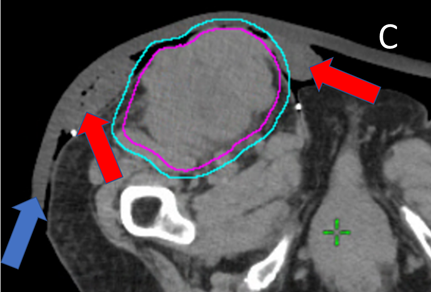

B Planning axial computed tomography (CT) scan through the volume showing the contour of the planning target volume (PTV) in light blue that was drawn by the RO. Half a centimetre of bolus was used to achieve the full dose to the skin.

C Planning axial CT showing the dosimetry with the dose wash option set to 44.83 Gy. The prescribed dose was 45Gy. This was accepted by the RO and treatment started.

D Halfway through treatment, the patient complained to the nurse of irritation within the external auditory canal (EAC). The nurse asked to see the planning axial CT showing dosimetry through the EAC with the dose wash option, this time set to 21.3 Gy, which is around half of the prescribed dose of 45 Gy. There is significant belling of the electron dose cloud into the EAC, which is lined by the epidermis, a hierarchically organised cell population. This is made worse by the air-filled EAC cavity as electrons can travel more freely in air than tissue. An acute radiation reaction of the skin in the EAC caused the symptoms.